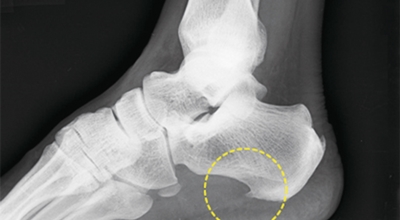

족저 근막이란 발가락 시작지점부터 발뒤꿈치뼈까지 발바닥 전체를 감싸고 있는 두꺼운 막을 말해요. 족저 근막은 발바닥 아치를 지속시켜 발바닥이 지면을 내딛음으로써 나타나는 충격을 흡수하는 중요한 역할을 수행하고 있어요. 이 족저 근막에 일차적으로 서서히 조직 손상이 일어나고 계속적인 활동으로 인해 염증이 커지면서 발 뒤꿈치 부근 통증을 유발하게 되는데 염증은 무리하고 반복적인 동작, 과도한 사용으로 마찰에 의해 발생해요.

주요 증상은 통증으로 발뒤꿈치 안쪽이 아주 아프며, 맨발로 바닥을 걸을 때 걸음을 내딛을 때마다 통증이 있어요. 가장 심한 통증은 아침에 일어나 첫 걸음을 뗄 때인데, 밤에 족저근막이 수축하다가 발에 체중이 가해지면서 갑자기 늘어나는 현상입니다.

비수술적 치료 방법에으로 보조기, 체외충격파, 스트레칭, 스테로이드 주사요법, 비스테로이드성 소염진통제 등이 여러 방법들이 있어요. 족저근막염 발생초기에는 스트레칭을하여 족저근막 또는 아킬레스건을 효과적으로 증가시키는 것만으로 추가적인 피해를 방지할 수 있죠. 그리고 보조기를 착용해서 뒤꿈치에 가해지는 충격을 완화 시킬 수 있어요. 발에 부종이 생긴 경우 진통주사를 이용해서 치료할 수 있어요. 수술적 치료로 들어가기 전 체외충격파를 이용해서 증상완화의 효과를 볼 수 있다고 해요.